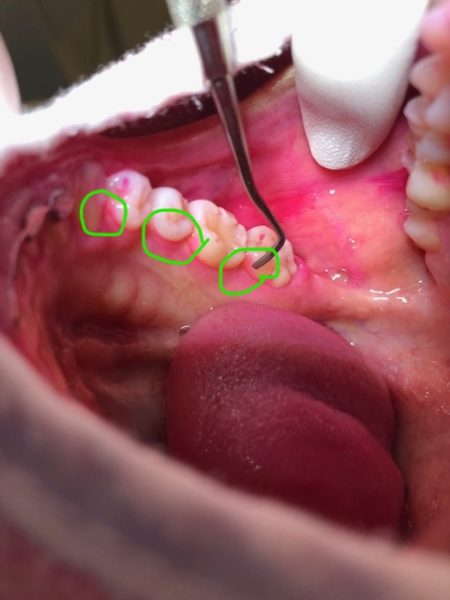

(↓お口の中の写真になりますのでご注意ください笑↓)

赤く染まっている部分が磨き残しです。

歯と歯の間や奥歯の内側にたっぷりと磨き残しが!!

歯ブラシで器用に磨いているつもりだったのですが

細かい部分が全く磨けていませんね・・・